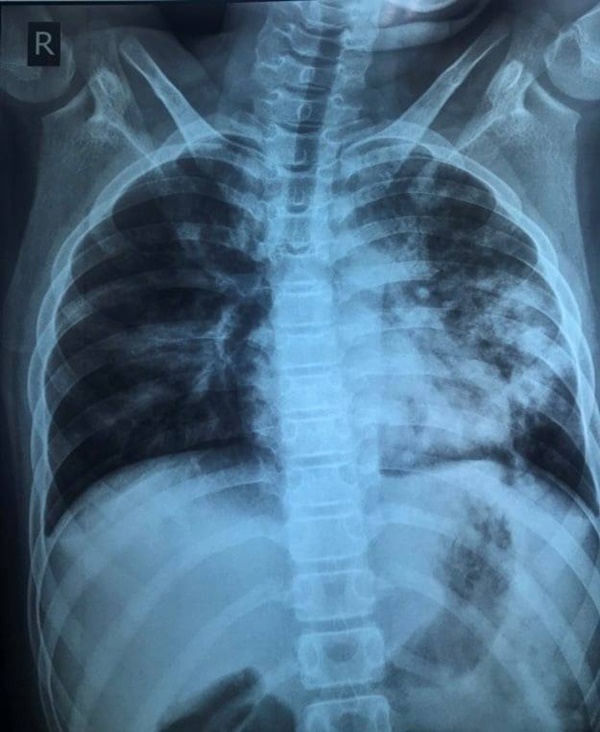

Hình ảnh X-quang phối của trẻ lúc nhập viện, tổn thương phổi nặng, dù triệu chứng rất kín đáo. Ảnh: BSCC.

Tại bệnh viện, nhịp thở của bệnh nhi 26-28 lần/phút, không quá nhanh so với tuổi. Tuy nhiên, chỉ số SpO2 của trẻ giảm xuống 92%, kết quả xét nghiệm PCR dương tính với nCoV. Kết quả chụp X-quang có tổn thương phổi nhiều, rối loạn đông máu.